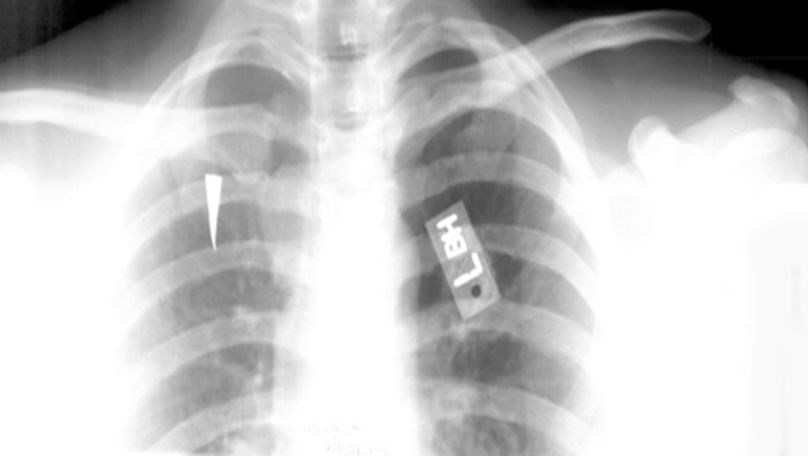

正常胸椎

疼痛科怎么理疗疼痛科医生、康复理疗科医生、针刀针灸医生应掌握的常见骨科疾病X光片_https://www.jmylbn.com_新闻资讯_第55张

胸椎压缩性骨折

疼痛科怎么理疗疼痛科医生、康复理疗科医生、针刀针灸医生应掌握的常见骨科疾病X光片_https://www.jmylbn.com_新闻资讯_第56张